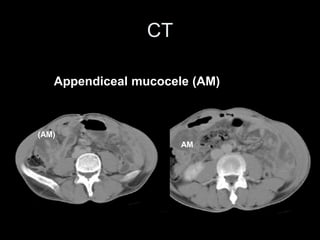

Pseudomyxoma peritonei (PMP) is a rare condition characterized by gelatinous ascites resulting from the rupture of appendiceal mucinous tumors, leading to significant abdominal complications. The incidence is approximately 2 cases per million per year, with a predominance in females, and diagnosis often relies on imaging techniques like ultrasound and CT scans. Effective treatment involves cytoreductive surgery combined with hyperthermic intraperitoneal chemotherapy (HIPEC) to manage disease progression and improve outcomes.